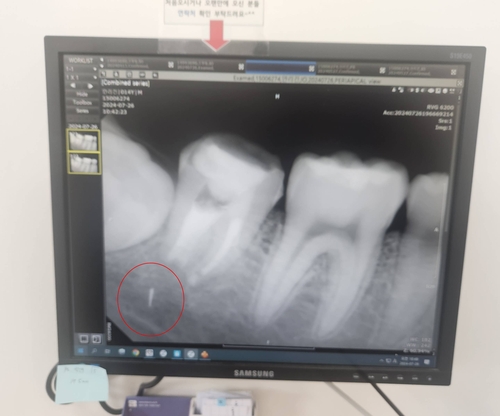

치과의원에서 신경치료를 받다가 파절된 의료기기 조각이 턱부위에 머무르고 있는 모습 [독자 제공. 재판매 및 DB 금지] |

그러나 치료 후에도 통증과 염증이 계속됐고, 한 달여 후 엑스레이 촬영을 통해 충격적인 사실을 확인했다. 치료 과정에서 부러진 의료기기 조각이 치아 뿌리에 남아 있었던 것이다. 안군의 성장에 따라 조각은 치아 뿌리에서 턱으로 서서히 이동하기까지 했다.

상급병원으로 옮긴 안군은 그해 가을 치아를 뽑고 턱뼈를 갈아내 조각을 제거한 뒤 다시 치아를 심는 수술대에 올랐다. 하지만 의료진은 수술 중 조각이 턱 신경과 너무 가까이 있어 무리하게 제거할 경우 신경 손상 위험이 크다고 판단했다. 결국 조각은 제거되지 못한 채 지금도 안군의 턱뼈 안에 박혀 있다.